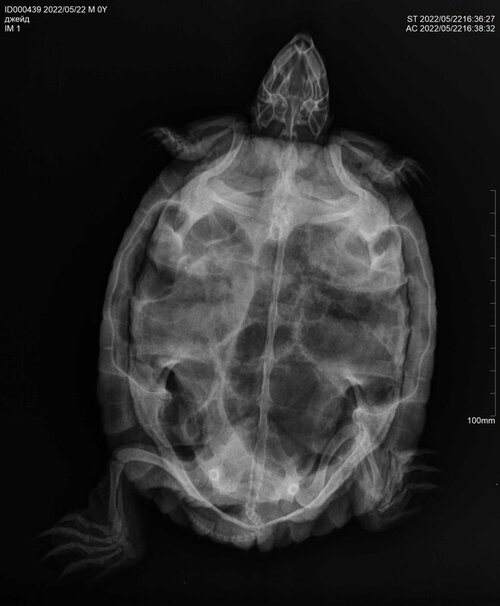

9. Вызов герпетолога на дом 21.04, ввел такие препараты: Тиенам, ронколейкин, гемобаланс, траумель, дюфалайт, катозал внутримышечно в попу, в каком количестве не знаю. Прописал Байтрил 2,5  1-2 капли припаивать 2 раза в день,10-14 дней. Гамавит 2-4 капли припаивать 2 раза в день 14 дней. Выполнил, параллельно через неделю начал закапывать в глаза тобрекс по 1 капле раз в день. Две недели черепаха часто дышит тяжело, с открытым ртом, издавая шипение, появляется какая то слизь. Соплей нет, неактивна, глаза постоянно закрыты, аппетит отсутствует. Находясь в воде выпускает пузыри изо рта. Делал периодически ромашковые ванны по полчаса, температура 28- 29 градусов и параллельно пытался кормить, ела по три четыре кусочка рыбы хек, креветки. 4 дня назад сделан укол Элеовита внутримышечно по калькулятору, два раза сделаны уколы борглюконата кальция подкожно, три раза поставлен зонд и введен Эспумизан по калькулятору. Вчера сделан рентген в двух проекциях. Требуется расшифровка. Улучшения состояния черепахи в течение всего месяца лечения нет, только ухудшение. Еще вспомнил, что перед заболеванием черепахи сломался нагреватель воды, и похоже всю ночь и день черепахи мерзли, температура воды опустилась наверное градусов до 18. Думаю это стало триггером к заболеванию, плюс нездоровое питание и еще не совсем правильное содержание. Записался к Токаревой Марии в Зоостатус на субботу 29. Хотел узнать продолжать ли лечение кальцием и Эспумизаном или ждать до очного осмотра? Спасибо.

@Nadbull к сожалению я снимки читаю плохо. Из того, что я вижу - сильные газы в жкт. Есть она с такими точно не будет.